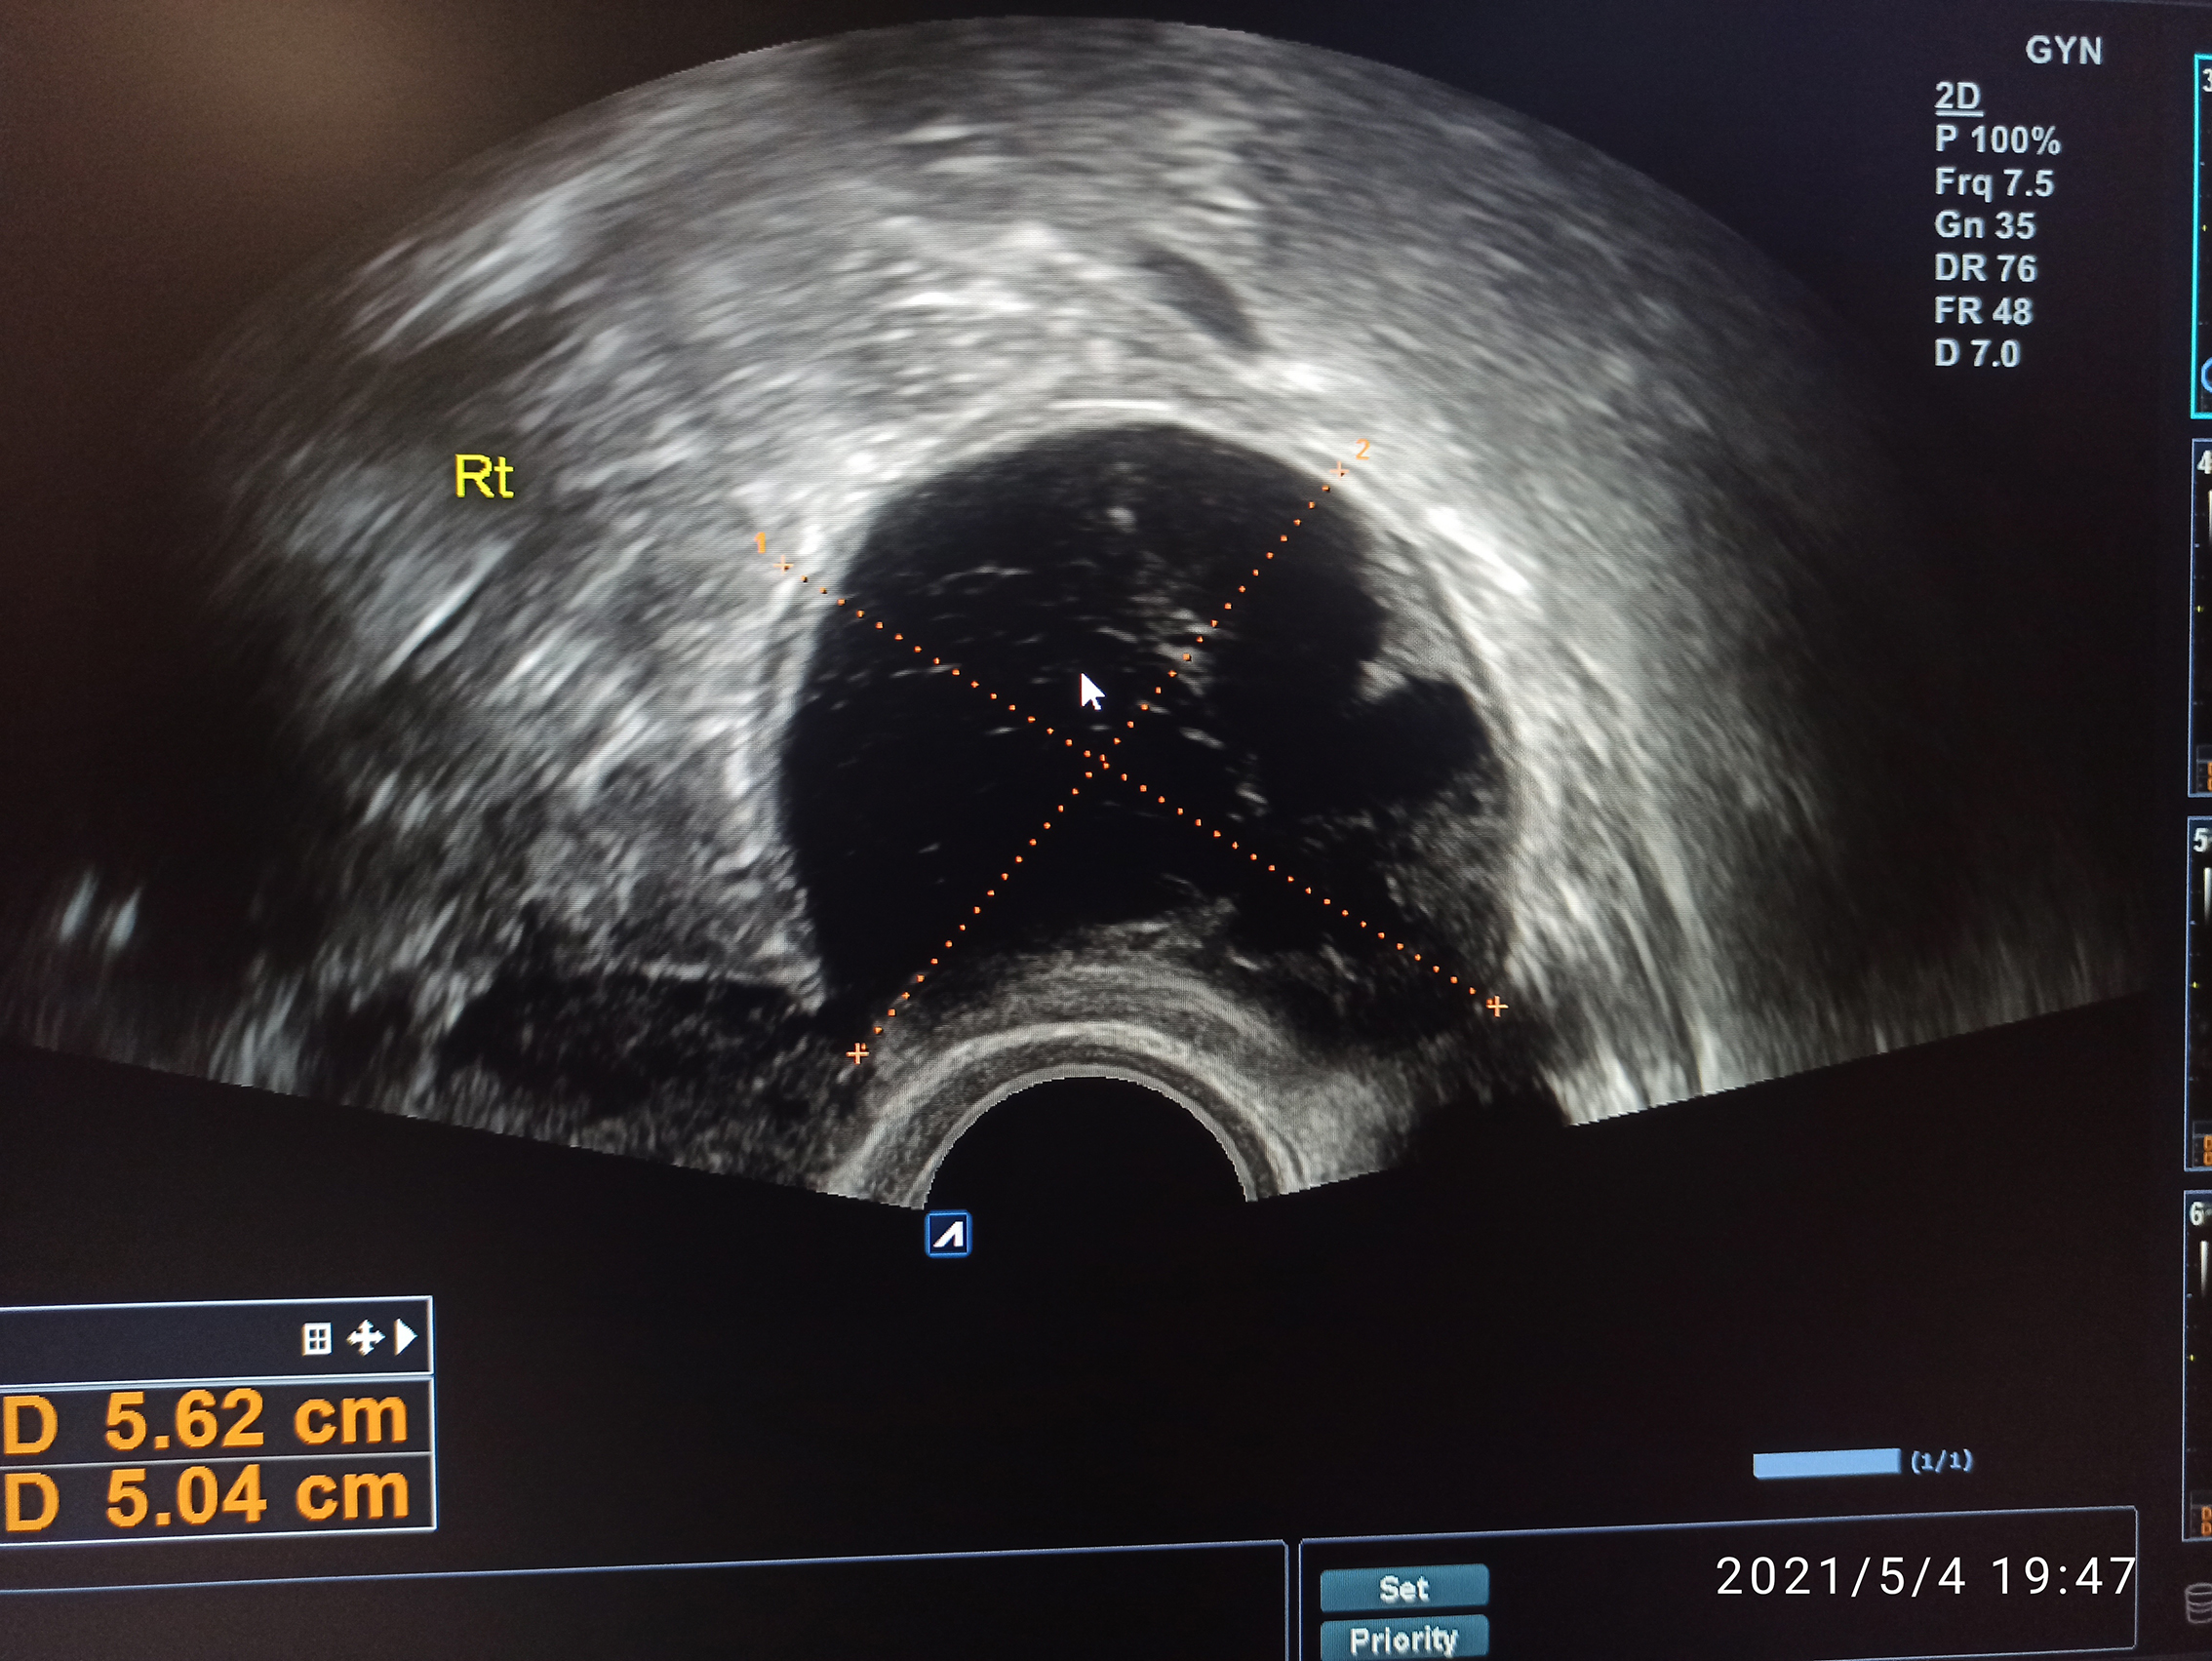

Pacjentka z zatrzymaniem miesiączki

30-letnia pacjentka zgłosiła się z powodu braku miesiączki, w 34 dniu cyklu, bez innych dolegliwości. Dotychczas miesiączkująca regularnie, co ok. 28 dni, miesiączki okresowo bolesne, okresowo obfite. Leków na stałe nie przyjmuje, chorób nie zgłasza. Rodziła raz siłami natury 6 lat wcześniej, poród i połóg bez powikłań. W badaniu przedmiotowym ginekologicznym: krocze, srom wieloródki, szyjka czysta, macica przodozgięta, przydatki bez zmian, tkliwe po stronie prawej.